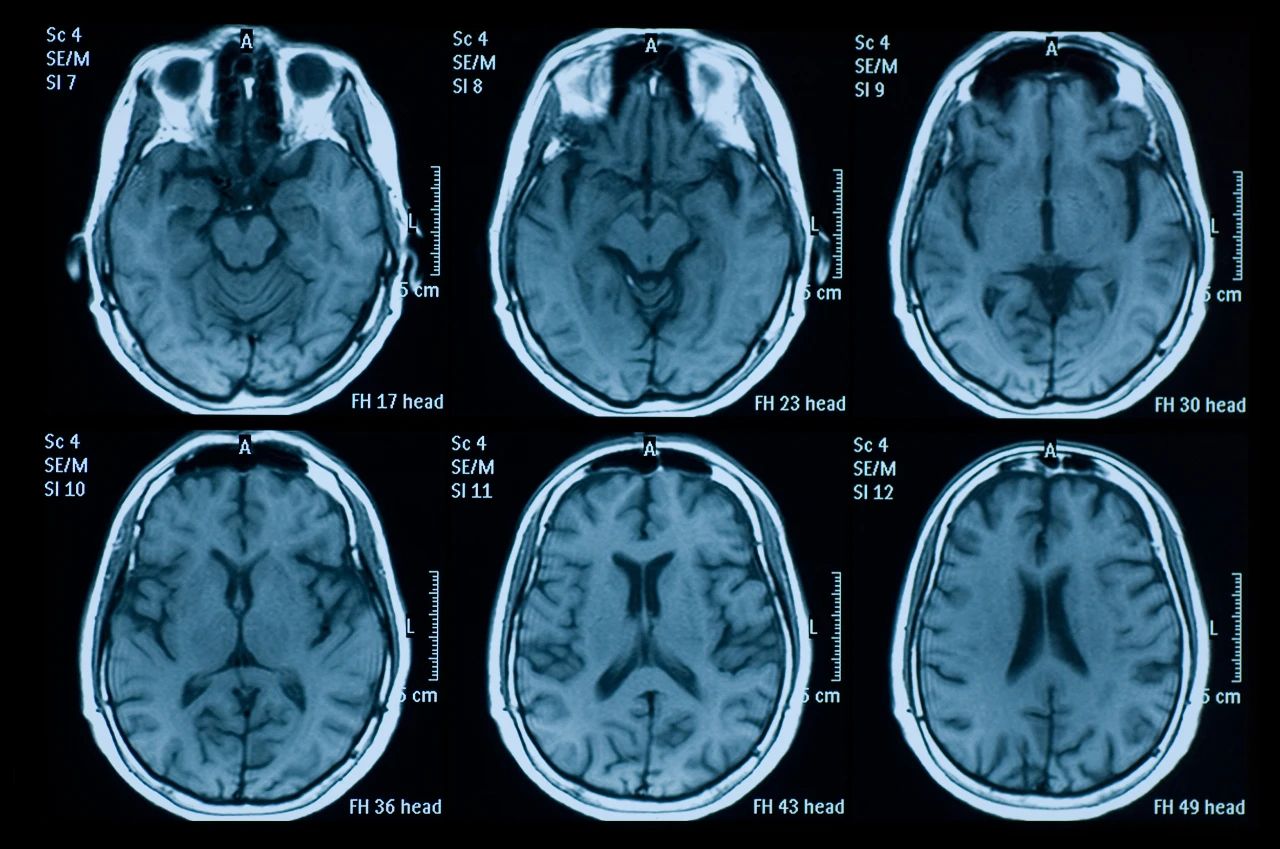

什么是創(chuàng)傷性腦損傷?

頭部受傷是頭部受到撞擊。它可能是輕微的,導(dǎo)致小腫塊或瘀傷,也可能更嚴(yán)重,導(dǎo)致腦損傷,如腦震蕩或腦出血。

即使您看不到頭部受傷也可能很?chē)?yán)重。它們可能導(dǎo)致永久性殘疾或損傷,甚至死亡。更嚴(yán)重的頭部受傷總是需要去看醫(yī)生。